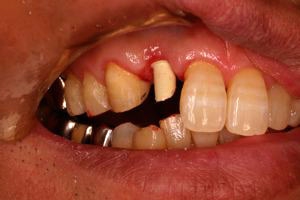

インセラム(オールセラミック)症例①

治療前治療前インセラム(オールセラミック)冠による修復。 主訴は前歯が汚い 金属を使わないオールセラミックでの治療を勧めた。 術前 治療後治療後術後